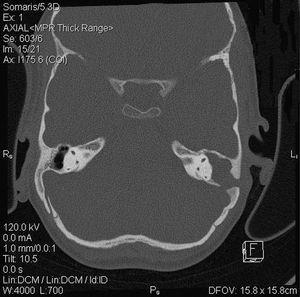

El examen físico revela buen estado general y apirexia. Presenta un aceptable estado de desarrollo y nutrición (peso: 21 kg [P10], talla: 121 cm [P50]). Destaca otorrea izquierda abundante con supuración abierta en la región mastoidea a través de fístula retroauricular (fig. 1), pero no hay signos de tumefacción mastoidea ni adenopatías regionales.

Figura 1.TC craneal: ocupación de todo el oído medio por masa de partes blandas. Las flechas señalan la ruptura de pared mastoidea interna y externa.

Tomografía computarizada (TC) craneal sin contraste con cortes en plano axial a nivel de oído medio con posterior reconstrucción en coronal: oído derecho, normal. Oído izquierdo con masa de partes blandas que ocupa caja, ático, antro y mastoides, con erosión de la cadena osicular. Oído interno, normal. Esclerosis mastoidea con defecto óseo por rotura en la pared externa de la mastoides correspondiente a fistulización retroauricular, y en la pared interna con comunicación a fosa posterior (fig. 1).